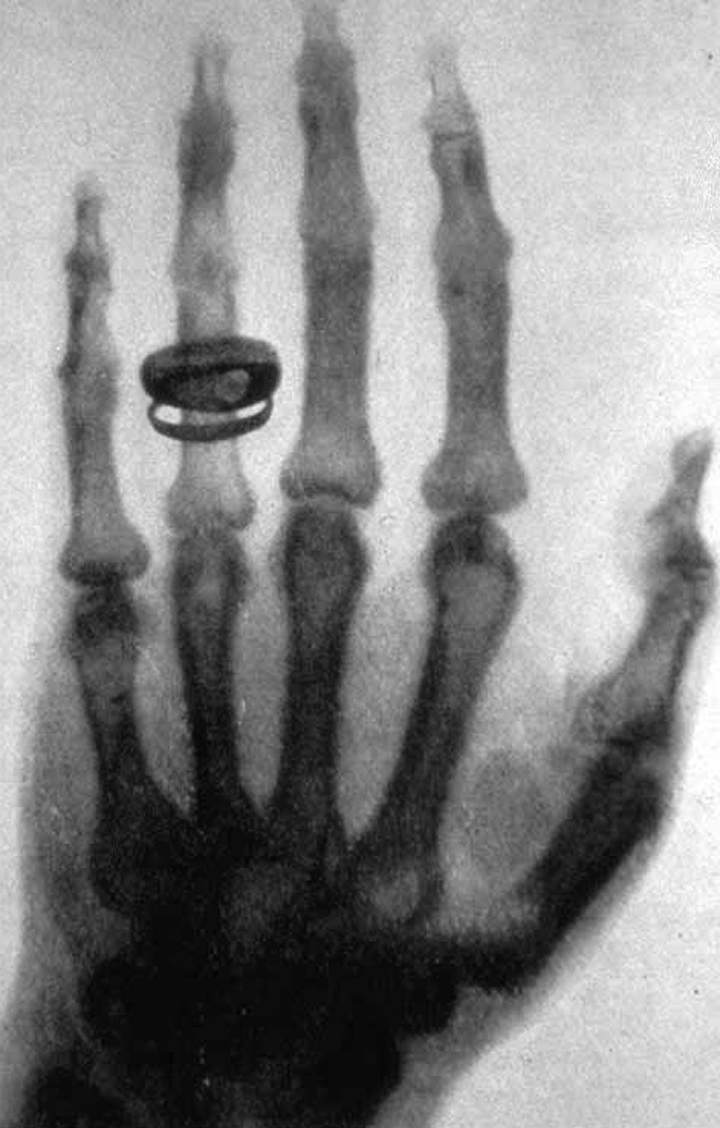

La quête de vérité occupe une place également centrale dans l’histoire de l’art occidental. Depuis l’Antiquité, les artistes tentent soit de refléter fidèlement la réalité visible – associée au vrai -, soit de révéler une certaine vérité. Dès le 4ème siècle avant J.-C., les philosophes grecs s’interrogent sur la capacité de la peinture et de la sculpture à la représenter. Platon introduit la notion de mimesis – l’imitation du réel – dans La République. Selon ce dernier, puisqu’une image imite le réel, elle ne peut donc être vraie ; pour Aristote, elle peut néanmoins permettre d’approcher une vérité universelle. Très vite s’impose néanmoins l’idée que l’observation de la réalité ne suffit pas à l’imiter. C’est par le recours à différentes techniques que des artistes de génie vont parvenir au fil des siècles à s’en approcher. Au Moyen-Age, l’art cherche davantage à suggérer une vérité spirituelle ; à partir de la Renaissance, de nouveau à imiter le réel. Avec le classicisme et à l’époque des Lumières, les artistes dépeignent la vérité de la condition humaine comme celle du progrès. Au 19ème siècle, le romantisme explore la vérité des sentiments ; le mouvement réaliste celle du quotidien. A partir du 20ème siècle, l’art interroge la réalité plus qu’il ne la dépeint afin de lui trouver un sens. « L’esthétique a renoncé à se sentir concernée de façon directe par le problème de la ressemblance convaincante, le problème de l’illusion artistique » comme le rappelle le grand spécialiste de l’histoire de l’art Gombrich dans l’art et l’illusion. C’est l’image photographique puis l’image animée qui saisissent et documentent dès lors la vérité du monde comme celle de l’homme : les missions de la FSA aux USA à la fin des années 30, la photo humaniste des années 40 et 50, le photojournalisme avec la naissance des news magazines et des agences de photos reporters, le film documentaire et les journaux TV… La photo scientifique amène à voir l’invisible (rayons X). L’avancée de la technologique repousse les limites levant toujours davantage le voile sur l’infiniment grand comme l’infiniment petit.